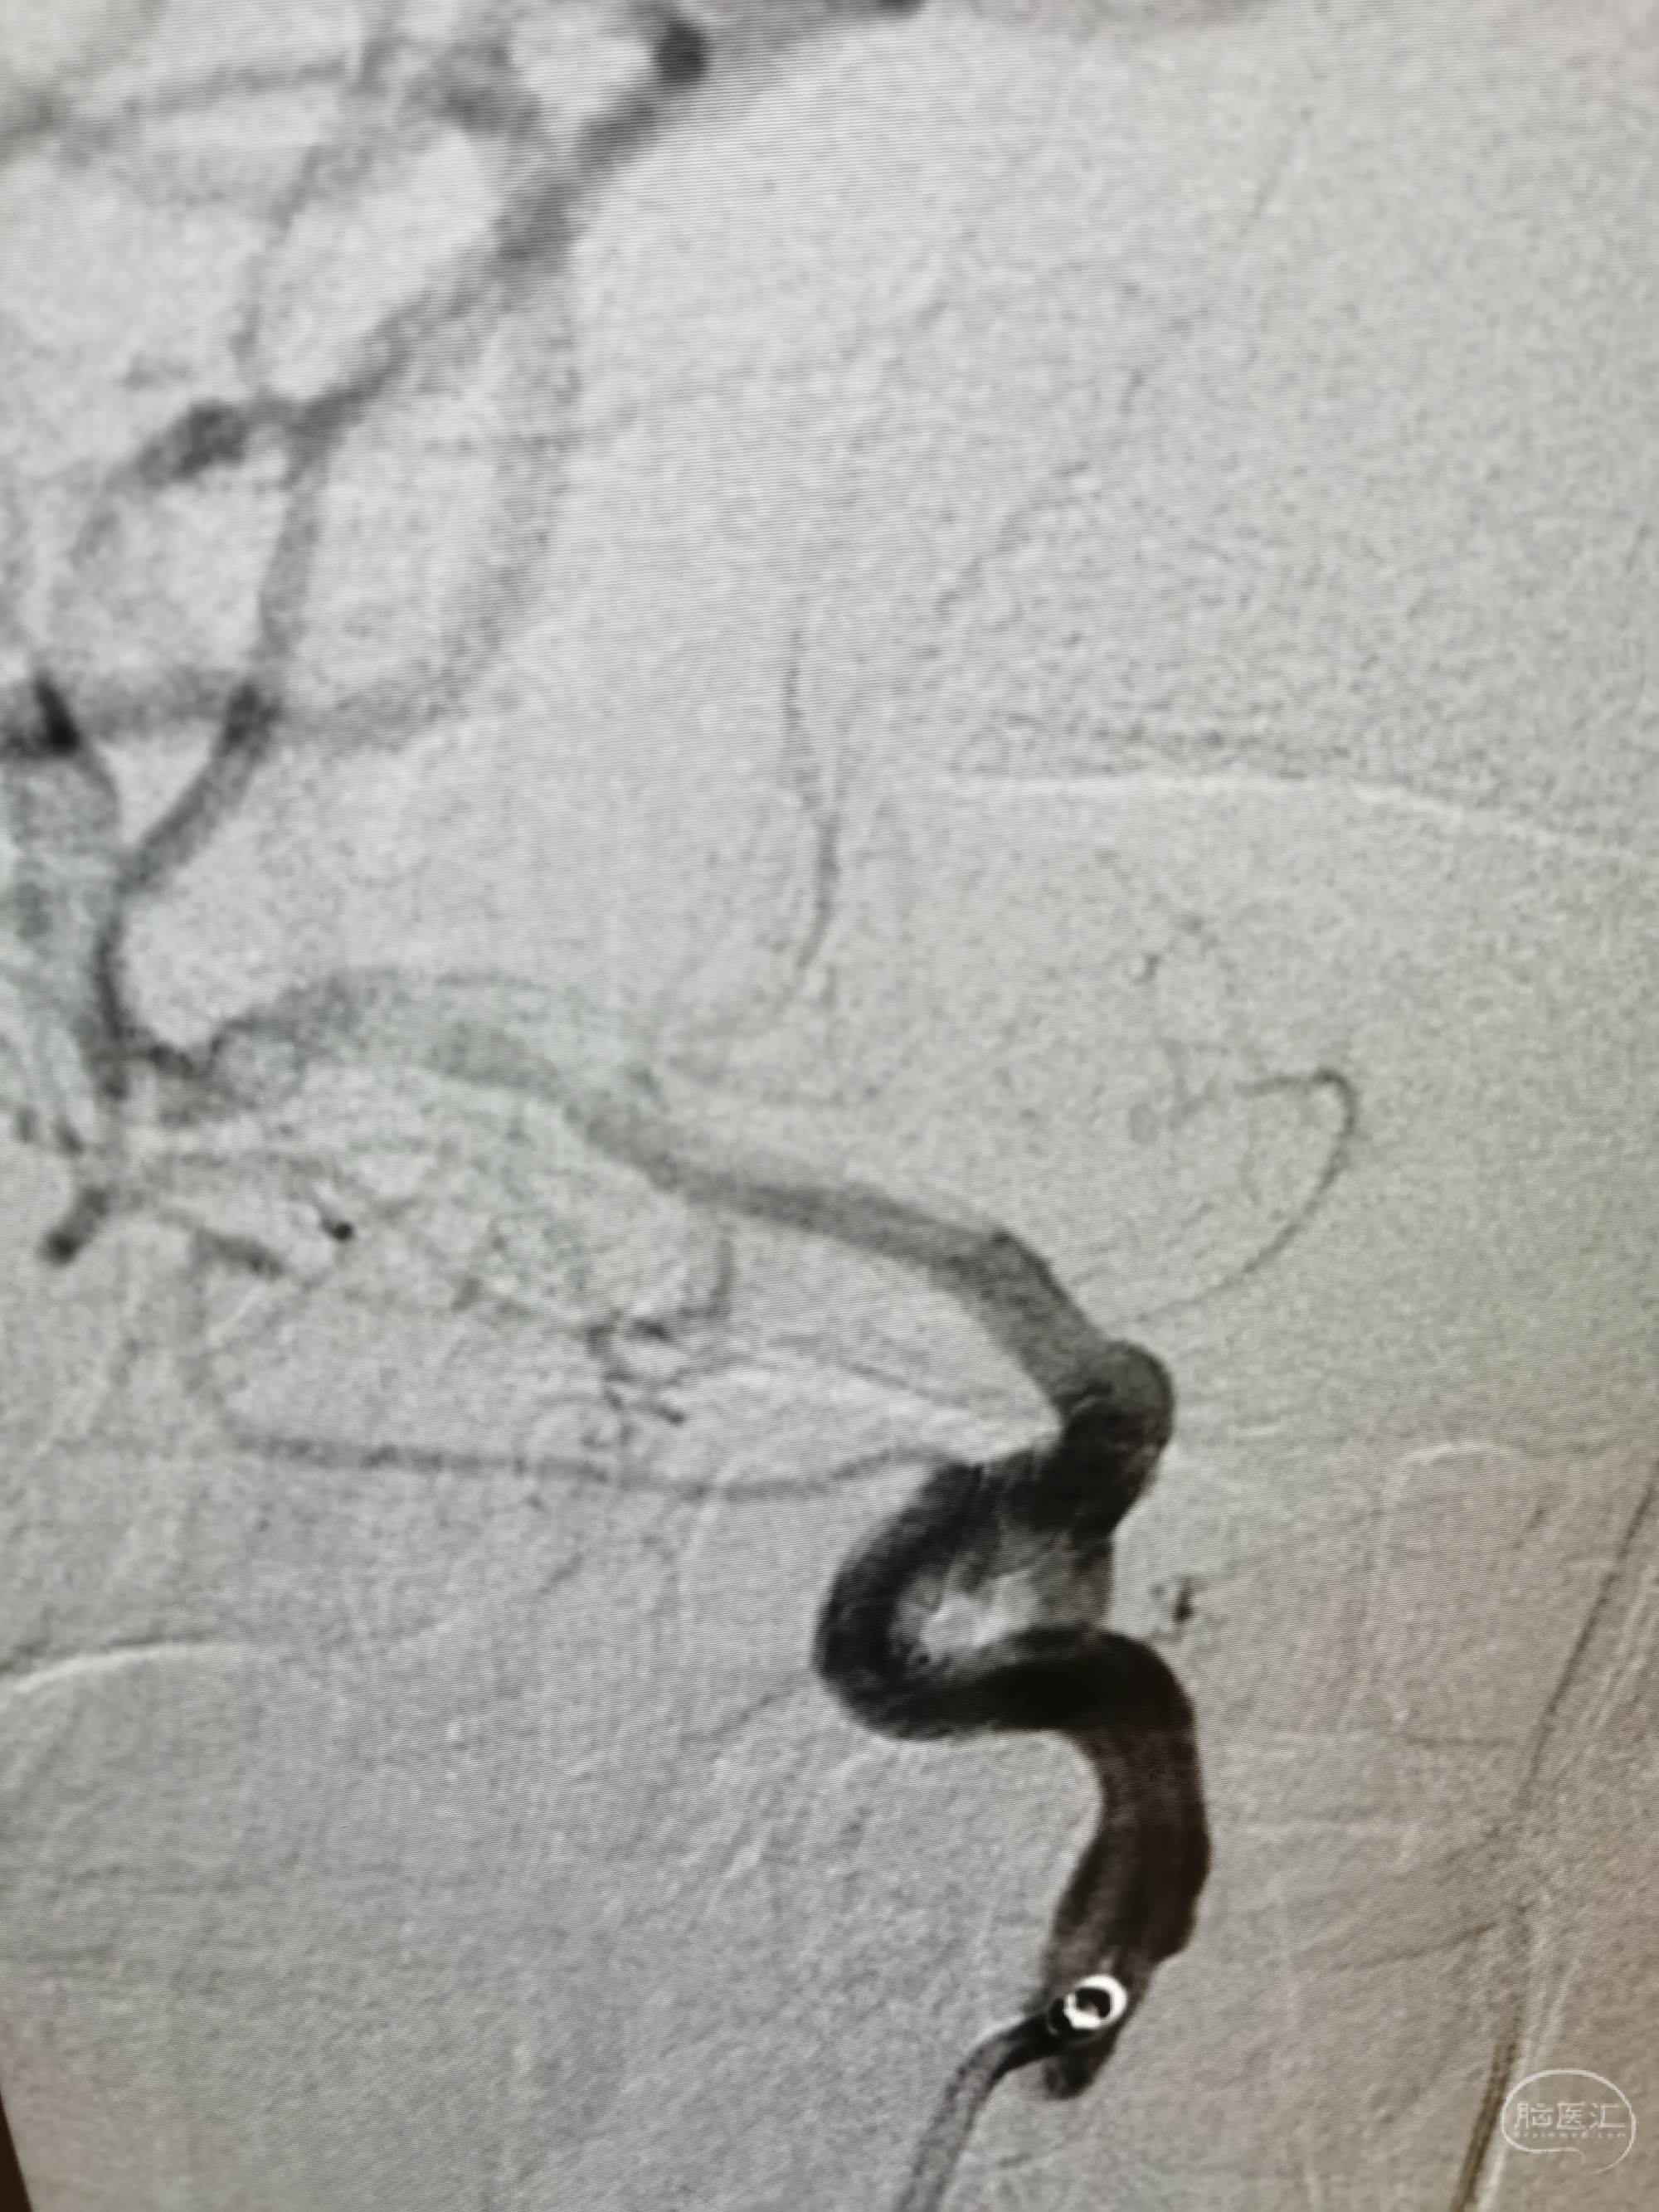

支架Atlas4.0×21mm辅助栓塞动脉瘤,支架放置后交通动脉。

target1.0×3.0,1.0×2.0mm两枚coiling.

动脉瘤栓塞良好。

后交通及载瘤动脉通畅。